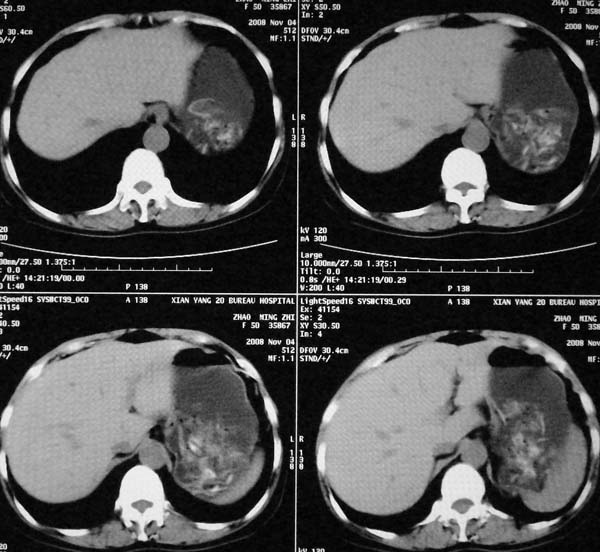

以下是引用dr.yang在2008-11-9 21:56:00的发言:[br]右肾上极占位?建议增强

以下是引用x-man在2008-11-9 22:30:00的发言:[br]建议先增强,右肾影明显增大,上极见边不清低密度肿块影,肿瘤待定.

以下是引用卜一在2008-11-10 8:09:00的发言:[br]建议先增强,右肾影明显增大,上极见边不清低密度肿块影,肿瘤待定.支持!另:第一次碎石是否肾受到损伤?合并感染?不知第一次碎石前是否做过彩超?

以下是引用dsl555在2008-11-9 23:57:00的发言:[br]建议先增强,右肾影明显增大,上极见边不清低密度肿块影,肿瘤待定. [br] [br]